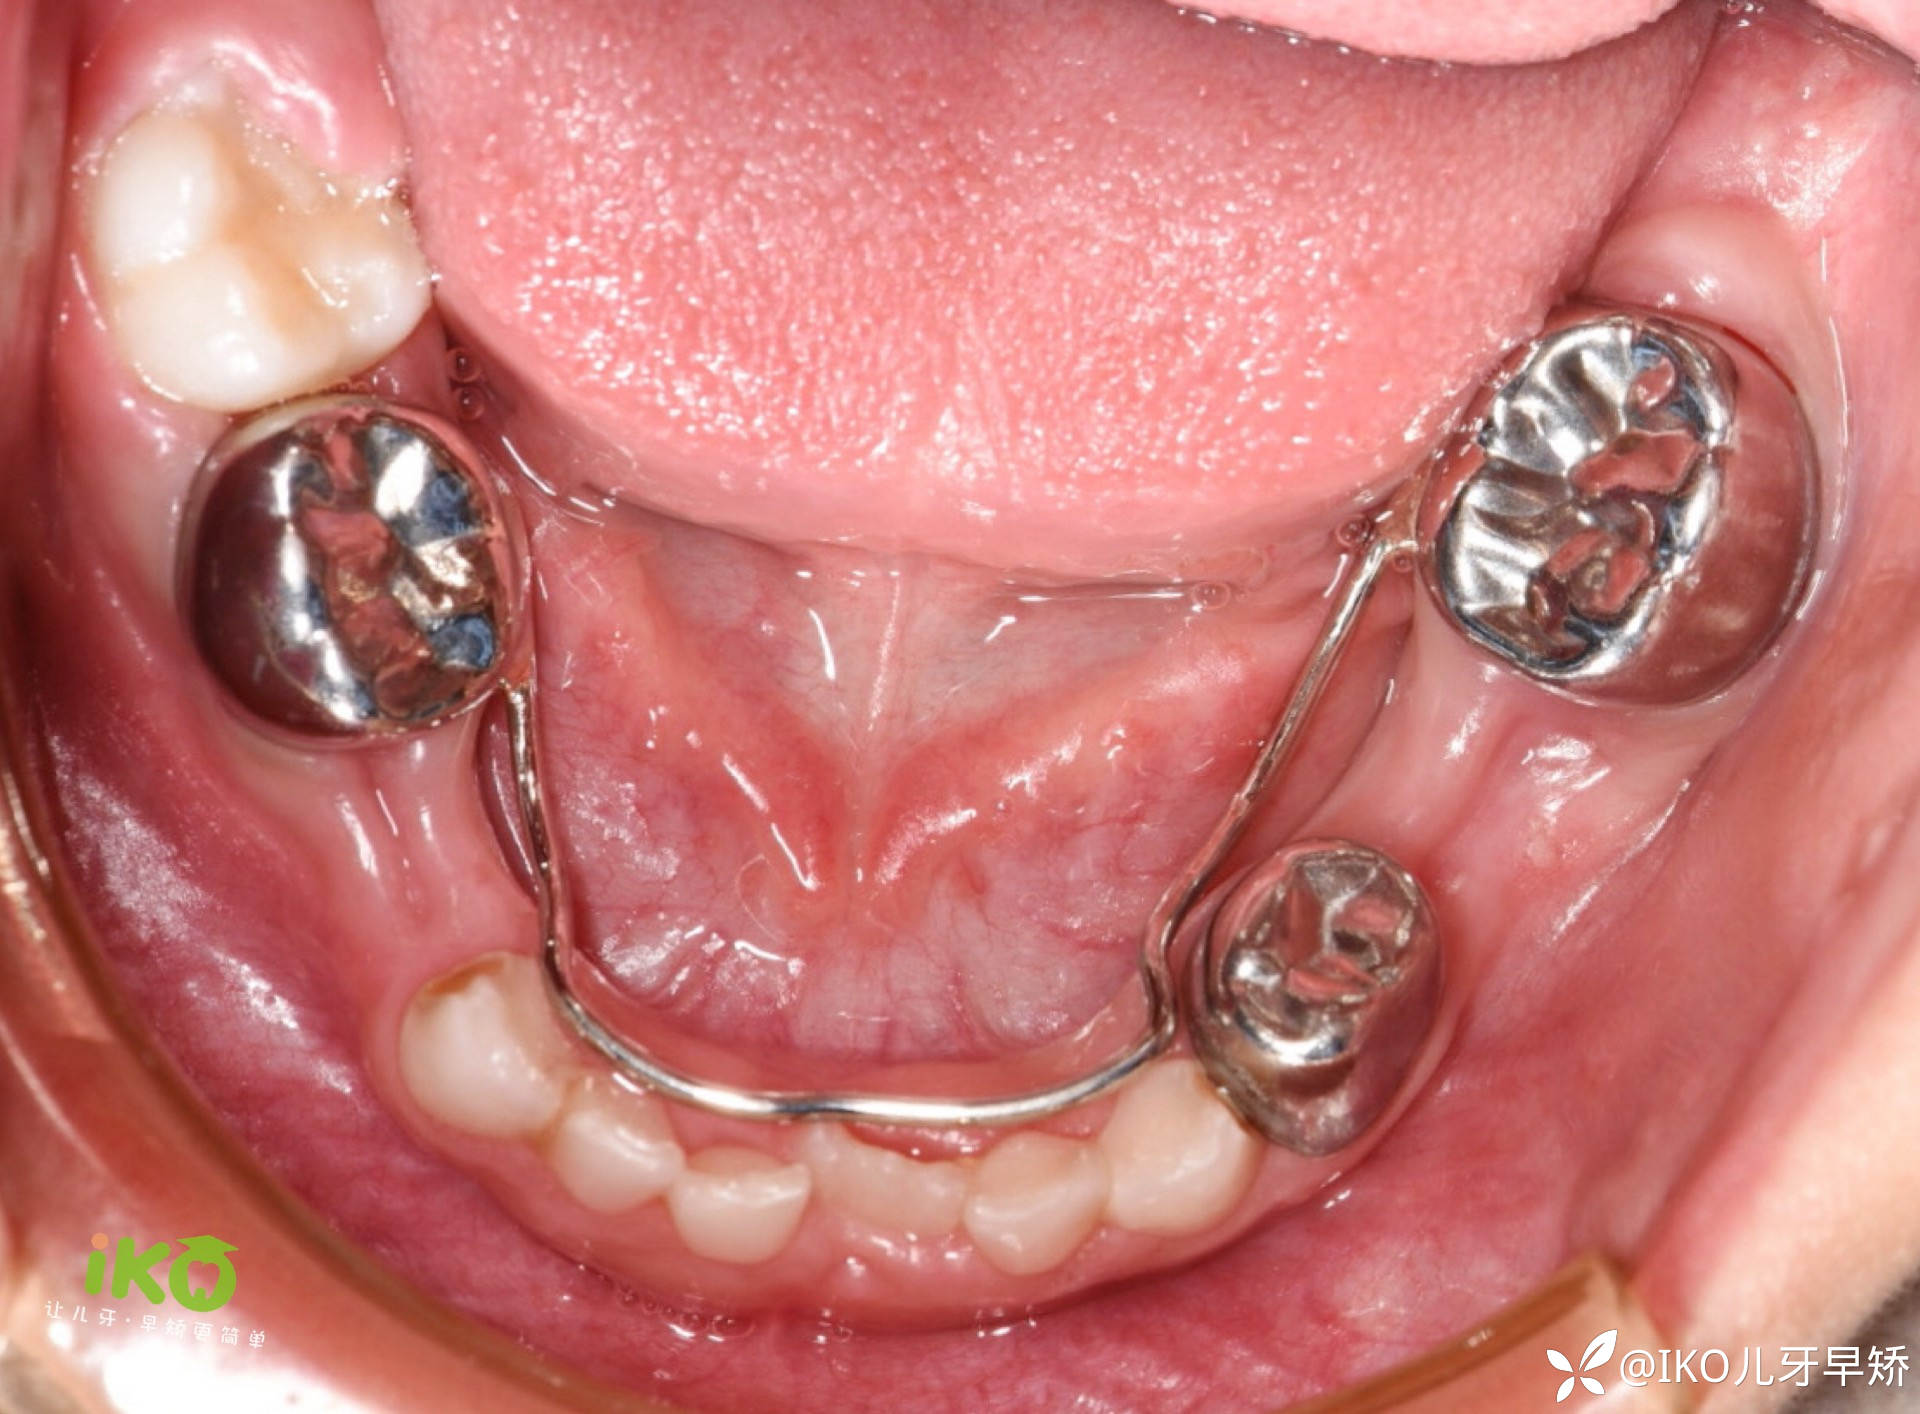

临床实战病例分享 · (二)

下颌舌弓式·间隙保持器制作流程:

临床操作步骤·⑴

临床操作步骤·⑵

结束🔚